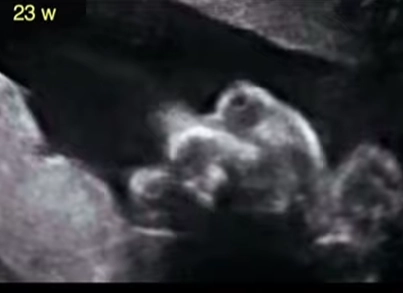

Nang túi lệ thai nhi (Dacryocystocele)

Tật mắt nhỏ và không có mắt ở thai (Microphthalmia and Anophthalmia)

Đục thủy tinh thể thai nhi (Cataracts)

Tật mắt lồi thai nhi (Proptosis)

Hai mắt gần nhau ở thai (Hypotelorism )

Tật hai mắt xa nhau thai nhi (Hypertelorism)